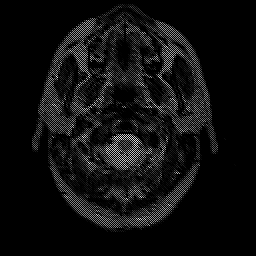

Glioma overlay -- Slice #1

[Home][Help][Clinical] Slice 1